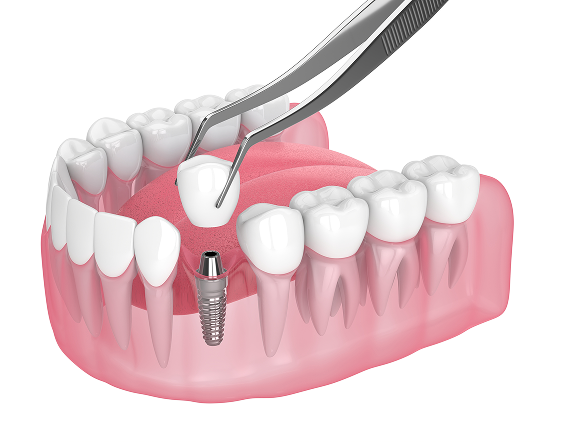

Single implants

If you have a single missing tooth, a dental implant is often the ideal solution. It serves as a replacement for the lost tooth root and provides support for the implant crown. Unlike traditional methods, it does not require grinding down adjacent teeth, preserving their natural structure. The implant functions like a natural tooth root by transferring chewing pressure from the crown to the jawbone, which helps maintain bone health and prevents resorption.